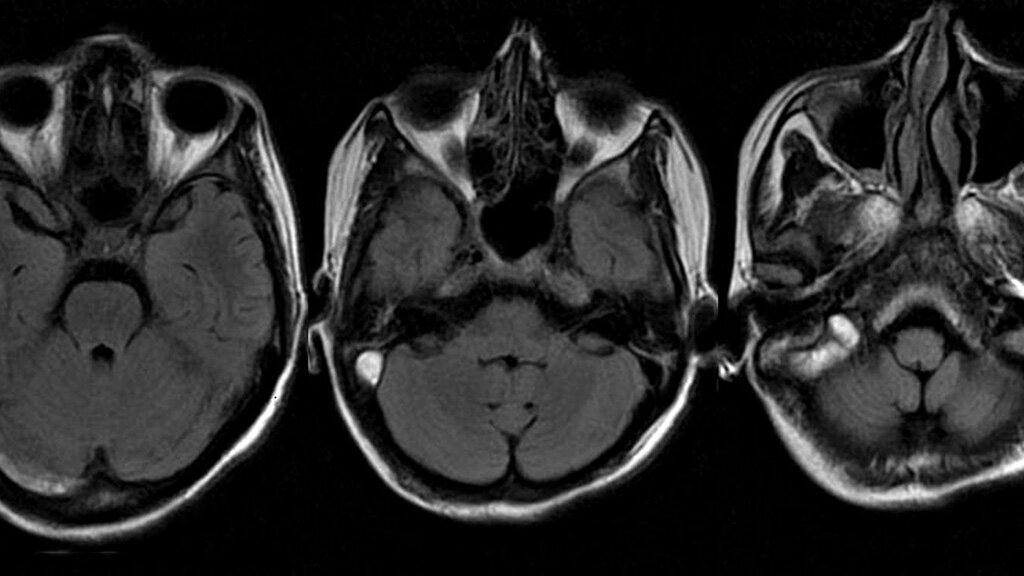

Как расшифровать результаты КТ носовых пазух?